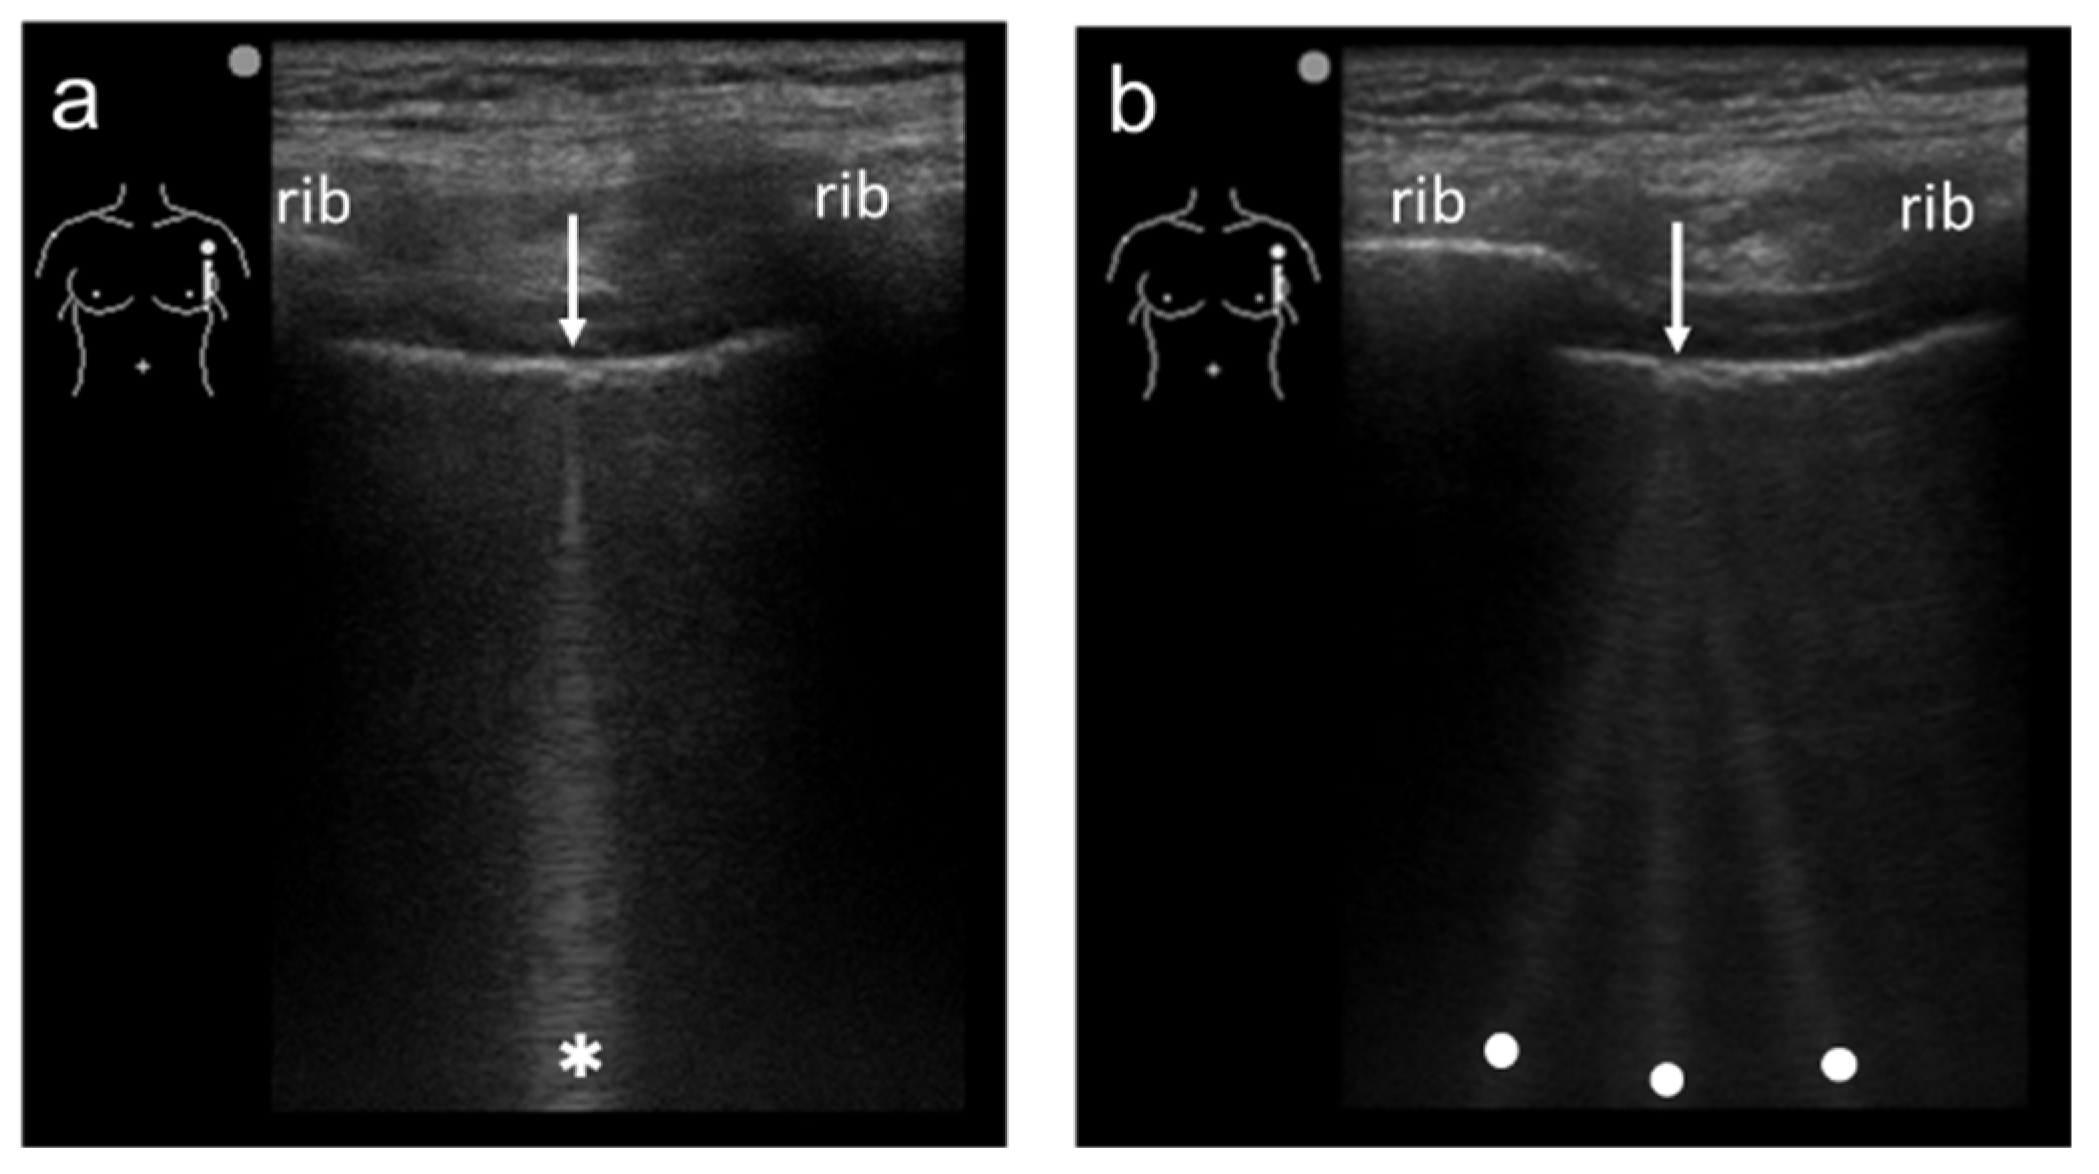

3.4. Selection of Transducers